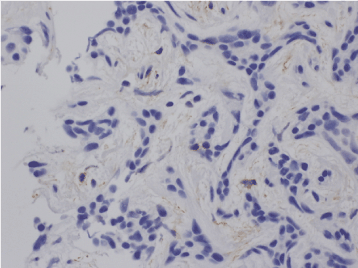

Histopathological analysis revealed that the excised specimen, a 3 ´ 4-mm opalescent tumor, contained a 1 ´ 2-mm mass of tumor tissue characterized by no clear borders and diffuse proliferation. Although tubular structures were observed in some areas, the degree of differentiation was low. And the surrounding tissue was characterized by strong hyalinization and basal membrane thickening. Tumor proliferation was mostly uniform, with no cribriform patterning (Figure 4). Immunohistological analysis revealed restiform proliferation of neoplastic myoepithelial cells strongly positive for vimentin and S-100. Although no completely cribriform structures were observed, cells showing intense staining for Ki-67 were (Figure 5). Based on these results, adenoid cystic carcinoma was diagnosed.

Figure 5.Cells showed intense staining for Ki-67 but no adenoid structures.

Tumors are generally solid, grayish white, nodular and solitary, ranging in size from 2 cm to 5 cm. Histopathologically, AdCC is characterized by relatively small, cubic or polygonal tumor cells resembling ductal epithelia and myoepithelial cells with eosinophilic cytoplasm. In typical AdCC, the parenchyma forms a cribriform lesion with microcystic cavities, although some tubular structures may be seen. Hyalinization of fibrous connective tissue is sometimes observed in the interstitium [1,2]. Low-grade pleomorphic adenocarcinoma and polymorphic adenoma need to be differentiated. In the present patient, no complete cribriform structures (a histopathological feature of AdCC) were observed, leading to a diagnosis of AdCC. In this case, some cells stained intensely for Ki-67, indicating a high level of cellular activity.